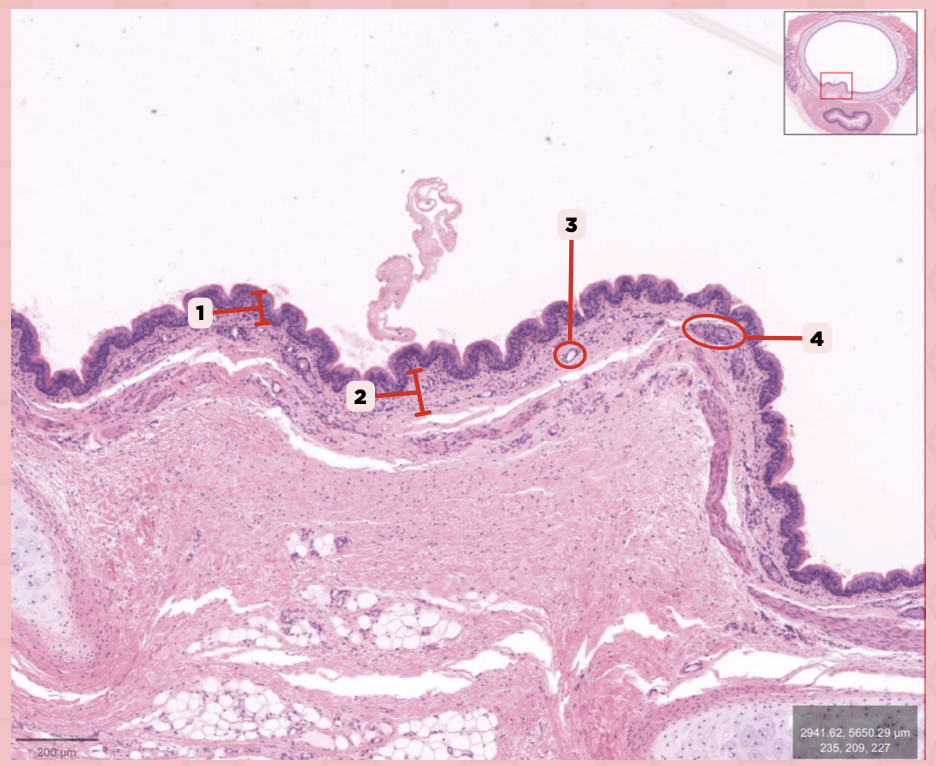

Identify the structure labeled as 1.

Nasal septum

Identify the structure labeled as 2.

Nasal cavity

Identify the structure labeled as 3.

Hard palate

Identify the structure labeled as 4.

Mucosal Associated Lymphoid Tissue (MALT)